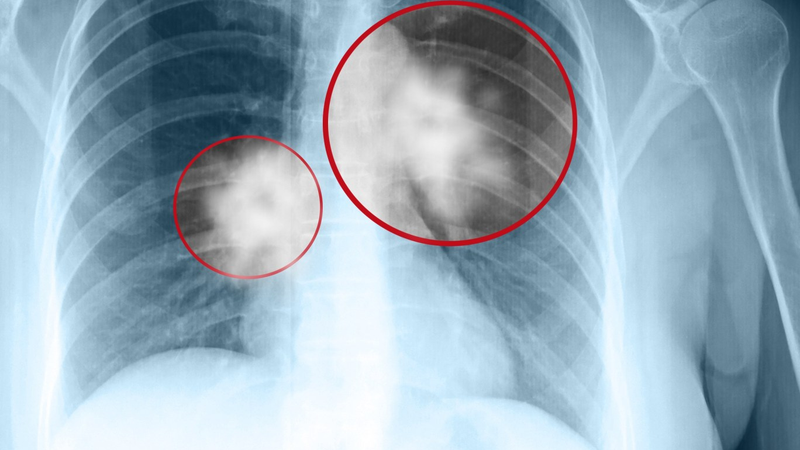

Chụp CT u phổi được xem là một trong những kỹ thuật hàng đầu dùng để chẩn đoán hình ảnh của phổi. Kết quả sau khi chụp CT sẽ đem đến ý nghĩa vô cùng quan trọng trong việc tối ưu quá trình chẩn đoán và tìm ra phương pháp điều trị phù hợp.

Việc chụp X quang phổi vẫn có nguy cơ bỏ sót khoảng 30% tổn thương. Còn đối với chụp CT u phổi, nó có thể giúp phát hiện phần lớn các vấn đề đang phát sinh ở tại phổi. Chính vì vậy, phương pháp này vô cùng tối ưu trong việc tìm ra những vấn đề tổn thương hoặc bệnh lý đang có ở phổi. Theo dõi nội dung của Nhà thuốc Long Châu để tìm hiểu chi tiết hơn về kỹ thuật chụp này.

Chụp CT u phổi chính là kỹ thuật để chẩn đoán các hình ảnh thông qua việc sử dụng chùm tia bức xạ X kết hợp với thiết bị chuyên dụng nhằm tạo ra hình ảnh cắt ngang đa chiều và đa lát các của cơ quan phổi. Kỹ thuật chụp này sẽ đem đến hình ảnh rõ nét và chi tiết hơn so với chụp X quang. Nó sẽ giúp bác sĩ phát hiện được các khối u phổi hoặc bệnh lý như viêm phổi, bệnh phổi kẽ,...

Kỹ thuật chụp cắt lớp phổi có thể tìm ra được các đám mờ nhằm đưa ra đánh giá chi tiết về khả năng tổn thương tại phổi. Phương pháp này sẽ giúp cho bác sĩ hạn chế tối đa tình trạng bỏ sót tổn thương ở phổi. Chụp CT phổi có thể đưa ra nhận dạng chi tiết nhất về các tổn thương, kích thước bị tổn thương và mức độ tổn thương.

Các hình ảnh CT thu được sẽ giúp cho bác sĩ tìm ra những tổn thương mà không thể quan sát được trước đó khi chụp X quang. Đây có thể do bị cơ hoành hoặc trung thất đã che lấp. Với kỹ thuật này, bác sĩ sẽ đánh giá được chi tiết về mức độ khối u với tốc độ di căn của chúng.